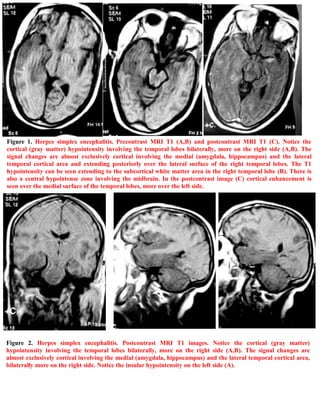

A 40-year-old female patient presented with fever, seizures, impaired consciousness, and signs of meningeal irritation. She was diagnosed with herpes simplex encephalitis. The document includes 6 figures showing MRI images of the brain that demonstrate abnormalities in the temporal lobes consistent with herpes simplex encephalitis. An addendum provides information on accessing updated versions and related publications on the editor's website.